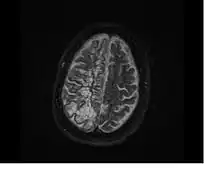

In humans, perivascular spaces surround arteries and veins can usually be seen as areas of dilatation on MRI images. While many normal brains will show a few dilated spaces, an increase in these spaces may correlate with the incidence of several neurodegenerative diseases, making the spaces a topic of research.[4]

Perivascular spaces are most commonly located in the basal ganglia and white matter of the cerebrum, and along the optic tract.[13] The ideal method used to visualize perivascular spaces is T2-weighted MRI. The MR images of other neurological disorders can be similar to those of the dilated spaces. These disorders are:[7]

Perivascular spaces are distinguished on an MRI by several key features. The spaces appear as distinct round or oval entities with a signal intensity visually equivalent to that of cerebrospinal fluid in the subarachnoid space.[7][14][15] In addition, a perivascular space has no mass effect and is located along the blood vessel around which it forms.[14]

Multiple sclerosis

Similar to the research concerning a potential connection between perivascular spaces and Alzheimer's, MRI scans of people recently diagnosed with multiple sclerosis (MS) have been studied. Larger, more prevalent spaces have been observed in those with MS.[28] Additional studies with similar findings have suggested that the inflammatory cells which contribute to the demyelination that characterizes MS also attack the perivascular spaces. Studies using advanced MRI techniques will be necessary to determine if the perivascular spaces can be implicated as a potential marker of the disease.[29]